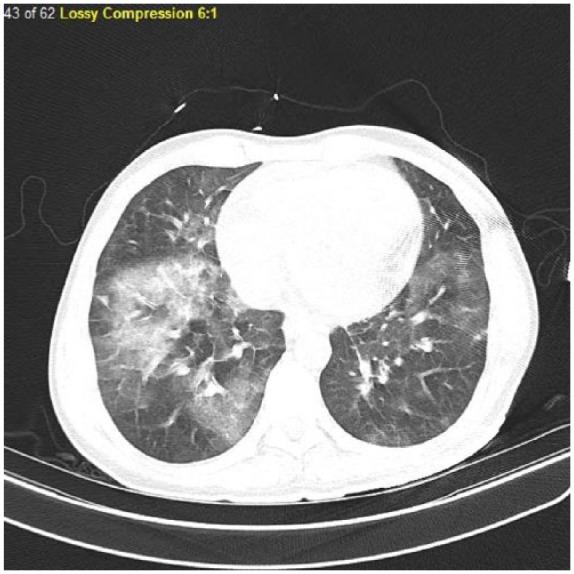

Eosinophilic myocarditis is an infiltrative disease that affects the myocardium leading to various presentations. It can be precipitated by medications, helminthiasis, or hypereosinophilic syndrome. We present the case of a young, male patient who presented with palpitations and dyspnea and was found to have heart failure with reduced ejection fracture of 12%. His past medical history was significant for recent lung problem treated with steroids. Based on his history and laboratory findings, he was started on intravenous steroids for treatment of eosinophilic myocarditis. Within 3 days, his ejection fracture improved to 35%. Given the nonspecific clinical presentations, mimicking other diseases, high index of suspicion is warranted to diagnose eosinophilic myocarditis. This is crucial as early detection and treatment with steroids can lead to a dramatic response.

嗜酸性粒细胞性心肌炎是一种浸润性疾病,可累及心肌并导致多种临床表现。它可能由药物、蠕虫感染或高嗜酸性粒细胞综合征引发。我们报告了一例年轻男性患者,该患者出现心悸和呼吸困难,经检查发现患有心力衰竭,射血分数降低至12%。他的既往病史显示近期因肺部问题接受了类固醇治疗。根据他的病史和实验室检查结果,开始给予静脉注射类固醇治疗嗜酸性粒细胞性心肌炎。3天内,他的射血分数提高到了35%。鉴于嗜酸性粒细胞性心肌炎的临床表现不具特异性,易与其他疾病混淆,因此需要高度怀疑以诊断该病。这至关重要,因为早期发现并用类固醇治疗可产生显著疗效。